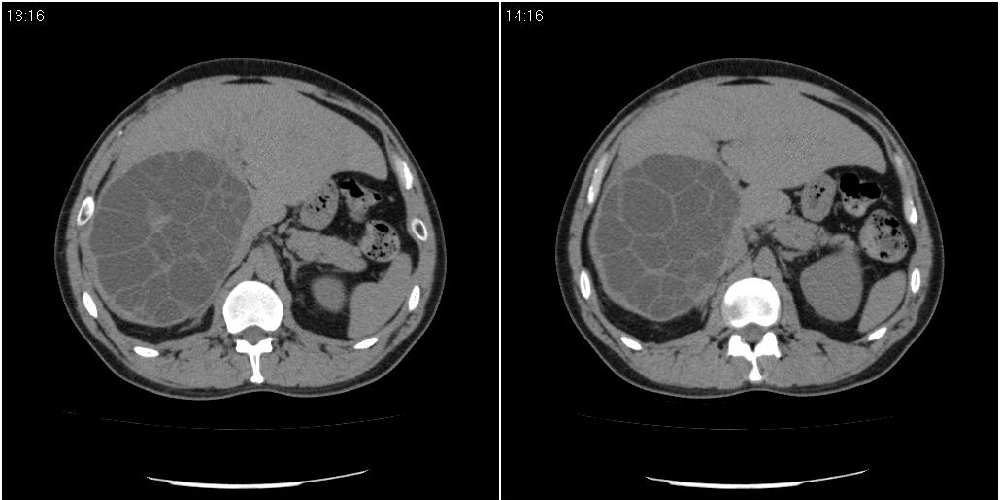

该患者70岁男性,手术后10年,现复查。2008年6月份本人曾经发过一极其类似的病例,只是部位略有差异。

肝脏多房性包虫囊肿

水上浮莲征,肝包虫囊肿。

肝脏及右侧胸腔包虫病。

大囊套小囊!肝脏多房性包虫囊肿